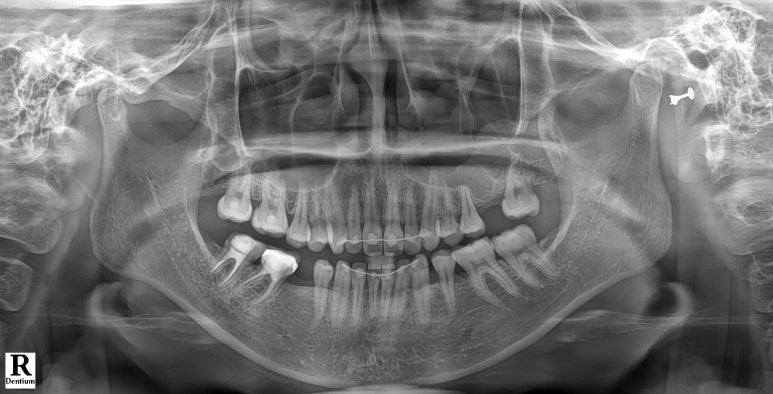

치과용 파노라마 엑스레이를 보니..

이미 전에 교정치료를 받으신 분이었어요.

그래서 치아는 가지런하신데, 치아의 모양과 색상을 개선하고 싶어 오신 분이었습니다!

아참! 빈 자리들은 임플란트 치료를 해드리기로 하였습니다.